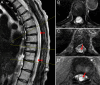

Observations: Here, the authors describe a 57-year-old female with a thoracic intradural arachnoid cyst that recurred despite extensive and initially successful fenestration. Given the failure of fenestration, the authors instead attempted to place a cystoperitoneal shunt. Given how extensive her laminectomy was, the authors elected to perform the procedure under ultrasonic guidance to avoid the large incision required for open shunt placement. The procedure was successful, with gradual improvement in the size of the arachnoid cyst as well as symptomatic improvement.